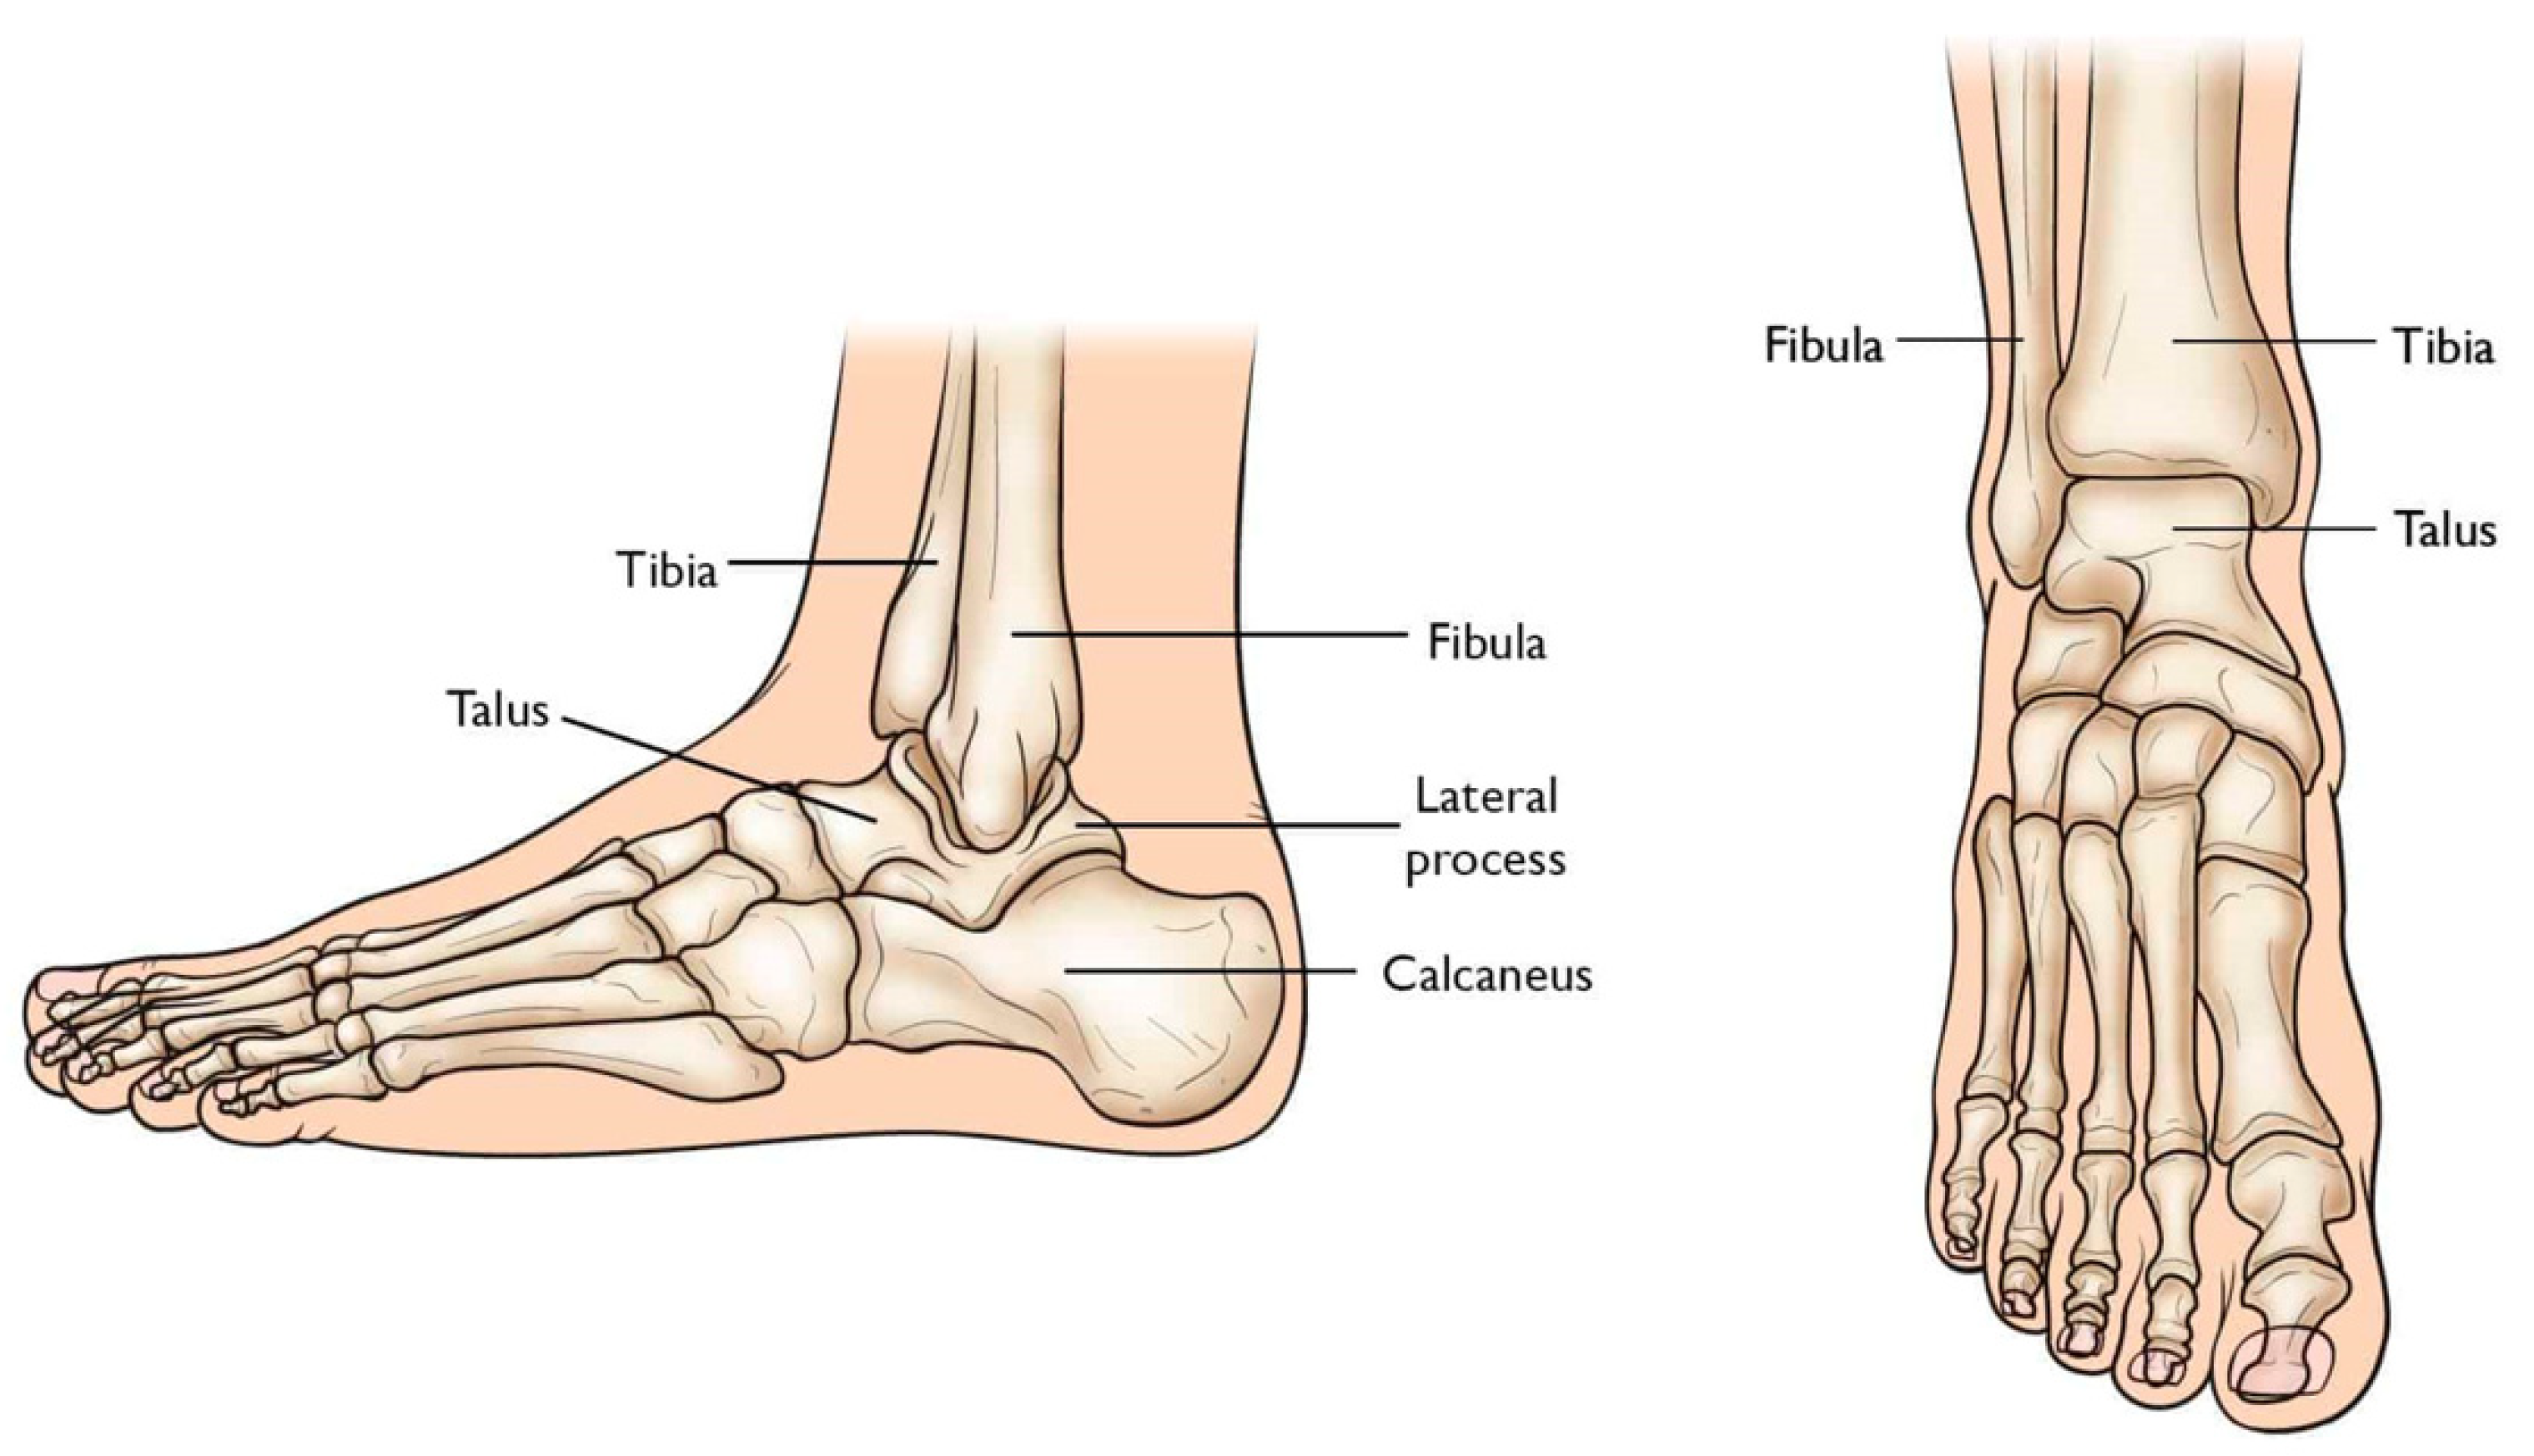

2. Total Ankle Replacement

3. Total Talus Replacement